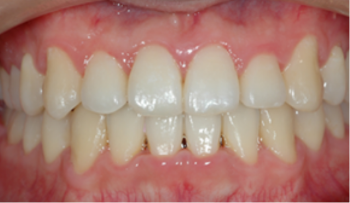

​​​​​​​Case 01. 덧니 & 치열 불규칙

덧니가 있거나 치열이 불규칙한 경우, 심미적으로도 보기에 좋지 않지만, 기능적으로도 본연의 역할을 상실하게 됩니다.

이 경우 교정 치료 방법은 크게 치아를 빼고 하는 방법과 치아를 빼지 않고 교정하는 방법으로 나뉩니다.

교정 치료 Before & After

• 덧니 & 치열 불규칙 교정 치료 전

Before

• 덧니 & 치열 불규칙 교정 치료 후

After